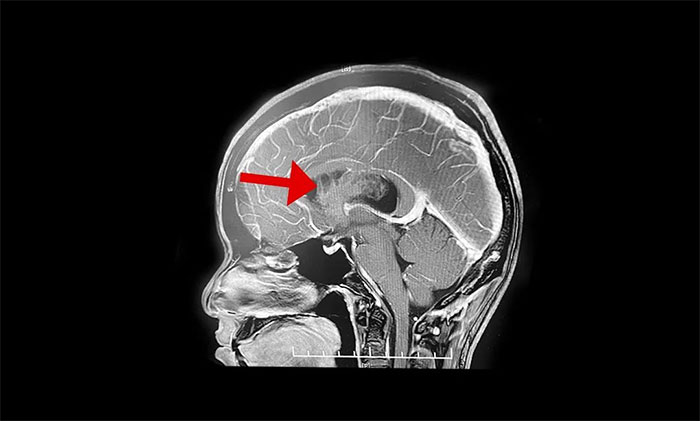

最終被診斷為中樞神經細胞瘤。中樞神經細胞瘤屬於比較罕見的腦腫瘤,一般直徑超過三公分即為巨大腫瘤,而李威腦室內的腫瘤直徑竟達七公分,接近一個拳頭大小。幸運的是,順利手術切除。

上海藍十字腦科醫院神經外科李士其教授介紹,中樞神經細胞瘤(Central neurocytoma,CN)是少見的神經系統腫瘤,1982年由Hansson首次報道並命名,2016年WHO神經系統腫瘤組織學分類將其歸類為神經元和混合型神經元膠質瘤(WHOⅡ級)。中樞神經細胞瘤僅佔顱內腫瘤的0.25%~0.50%,好發於20~40歲青年人,無性別差異。病史一般較長,可達數十年之久,好發於側腦室透明隔,當病變累及Monro孔時,阻塞腦脊液循環,引起頭痛、頭暈、惡性、嘔吐以及不同程度視力改變等非特異性顱內高壓症狀。

李士其教授介紹,該腫瘤一般生長於側腦室或三腦室,由於生長的位置處於腦室內,有較大空隙代償,疾病初期症狀並不典型,當出現如頭痛、嘔吐等臨牀症狀時,瘤體已經比較大。在治療上首先建議進行手術切除,解除腫瘤佔位效應,通暢腦脊液通路,緩解腦積水,解除顱內高壓。李士其教授指出,中樞神經細胞瘤一般為偏良性腫瘤,若能手術全切腫瘤,或者大部分切除後輔助放療可以長期生存。所以,手術這一步非常關鍵。